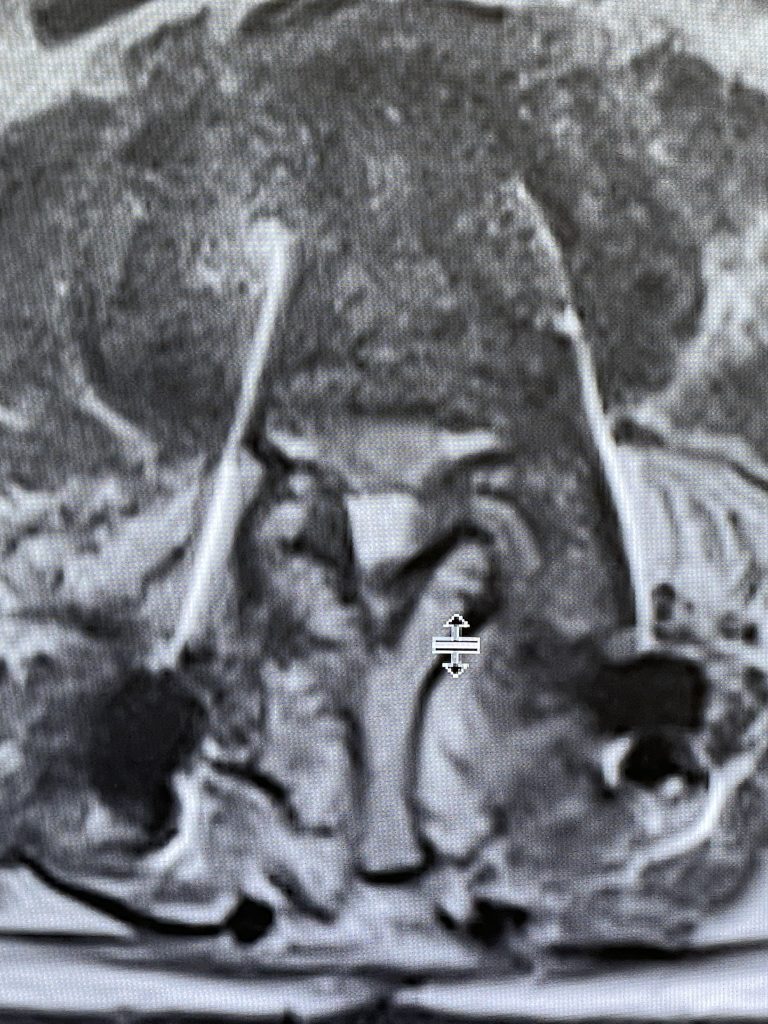

Figure 2. Axial T2 MRI of the lumbar spine demonstrating L2-3 stenosis due to significant facet arthropathy.

This 62-year-old female presents with chronic intractable low back pain with radiation down the front of her thighs. The patient had had two prior fusion surgeries: She initially had an L4-S1 fusion twelve years prior and a subsequent revision extension of her fusion at L3-4 that she had three years prior. She had a long-term history of smoking. She had mild hip flexor weakness, right greater than right. Imaging studies revealed next segment degeneration and stenosis at L2-3. (Figs. 1a and 1b and 2).